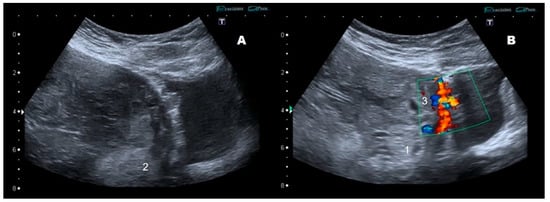

2. Case Report